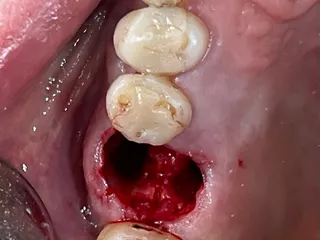

5. Occlusal view after atraumatic tooth extraction.

5